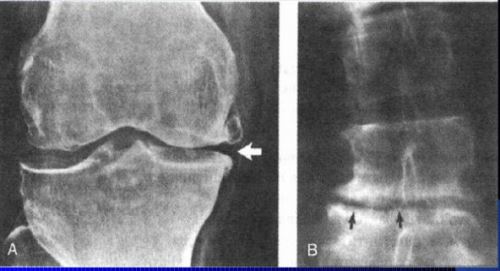

Субхондральный остеосклероз (поражение суставных поверхностей) выступает рентгенпроявлением артроза.

Субхондральный остеосклероз суставных поверхностей – это подхрящевая форма.

Костная ткань в момент повреждения хрящевого слоя, покрываемого суставные поверхности, уплотняется и разрастается в процессе развития. На ее поверхности образуются остеофиты — наросты, выполненные из костной ткани. Описанные остеообразования иногда могут располагаться на самом краю хряща и совершенно не препятствовать движению. Однако, в другом случае наросты прорастают между поверхностями диартроза и сужают суставную щель. Тогда суставная двигательная способность нарушена и во время функционирования может сопровождаться болевым ощущением.